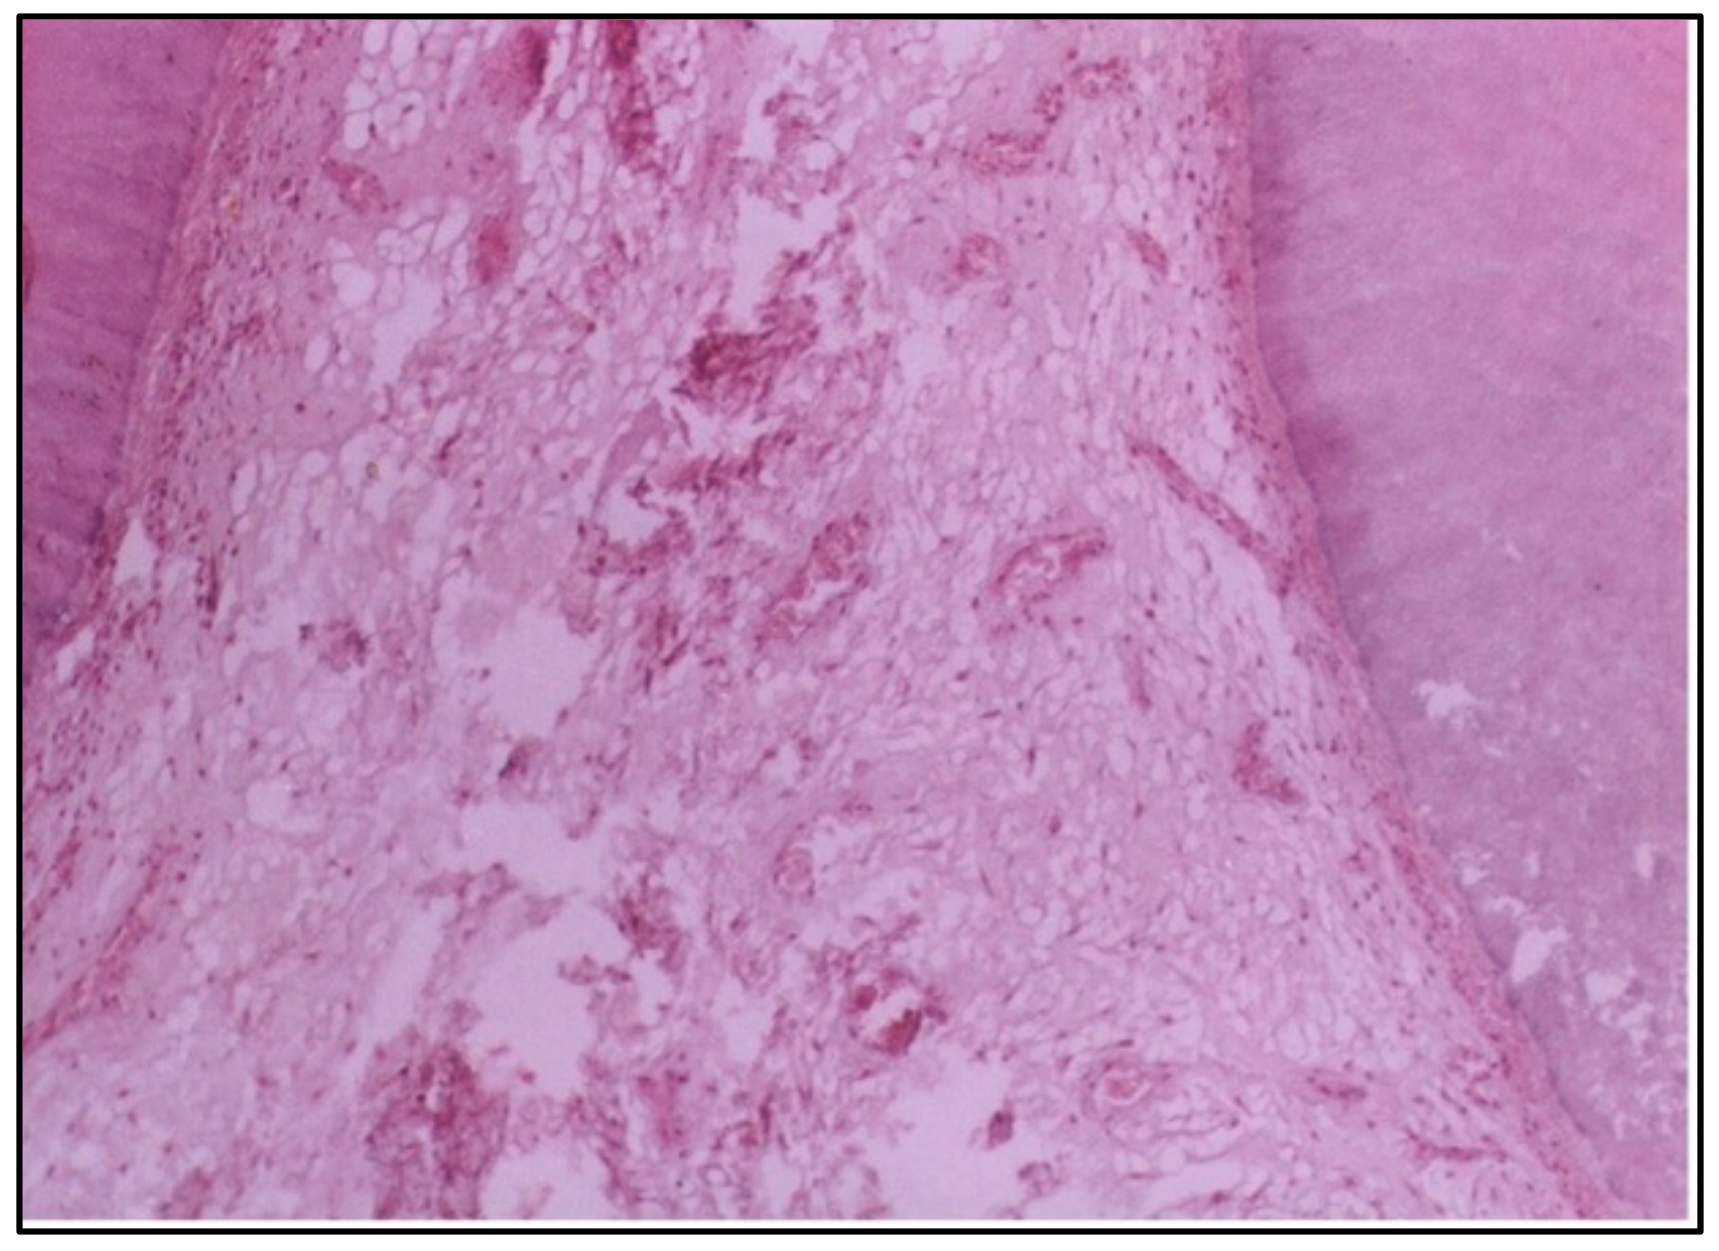

At 6 weeks, the damage was even more severe, with massive destruction of the pulp tissue, including the formation of a large abscess. This level of destruction indicates that the pulp could not withstand the long-term effects of the conventional composite resin, leading to extensive tissue necrosis and infection (Figure 5).

Figure 5. LS of the pulp (Group II, 6 weeks) showing massive destruction of the pulp tissue with an abscess formation (H & E Stain, ×100).